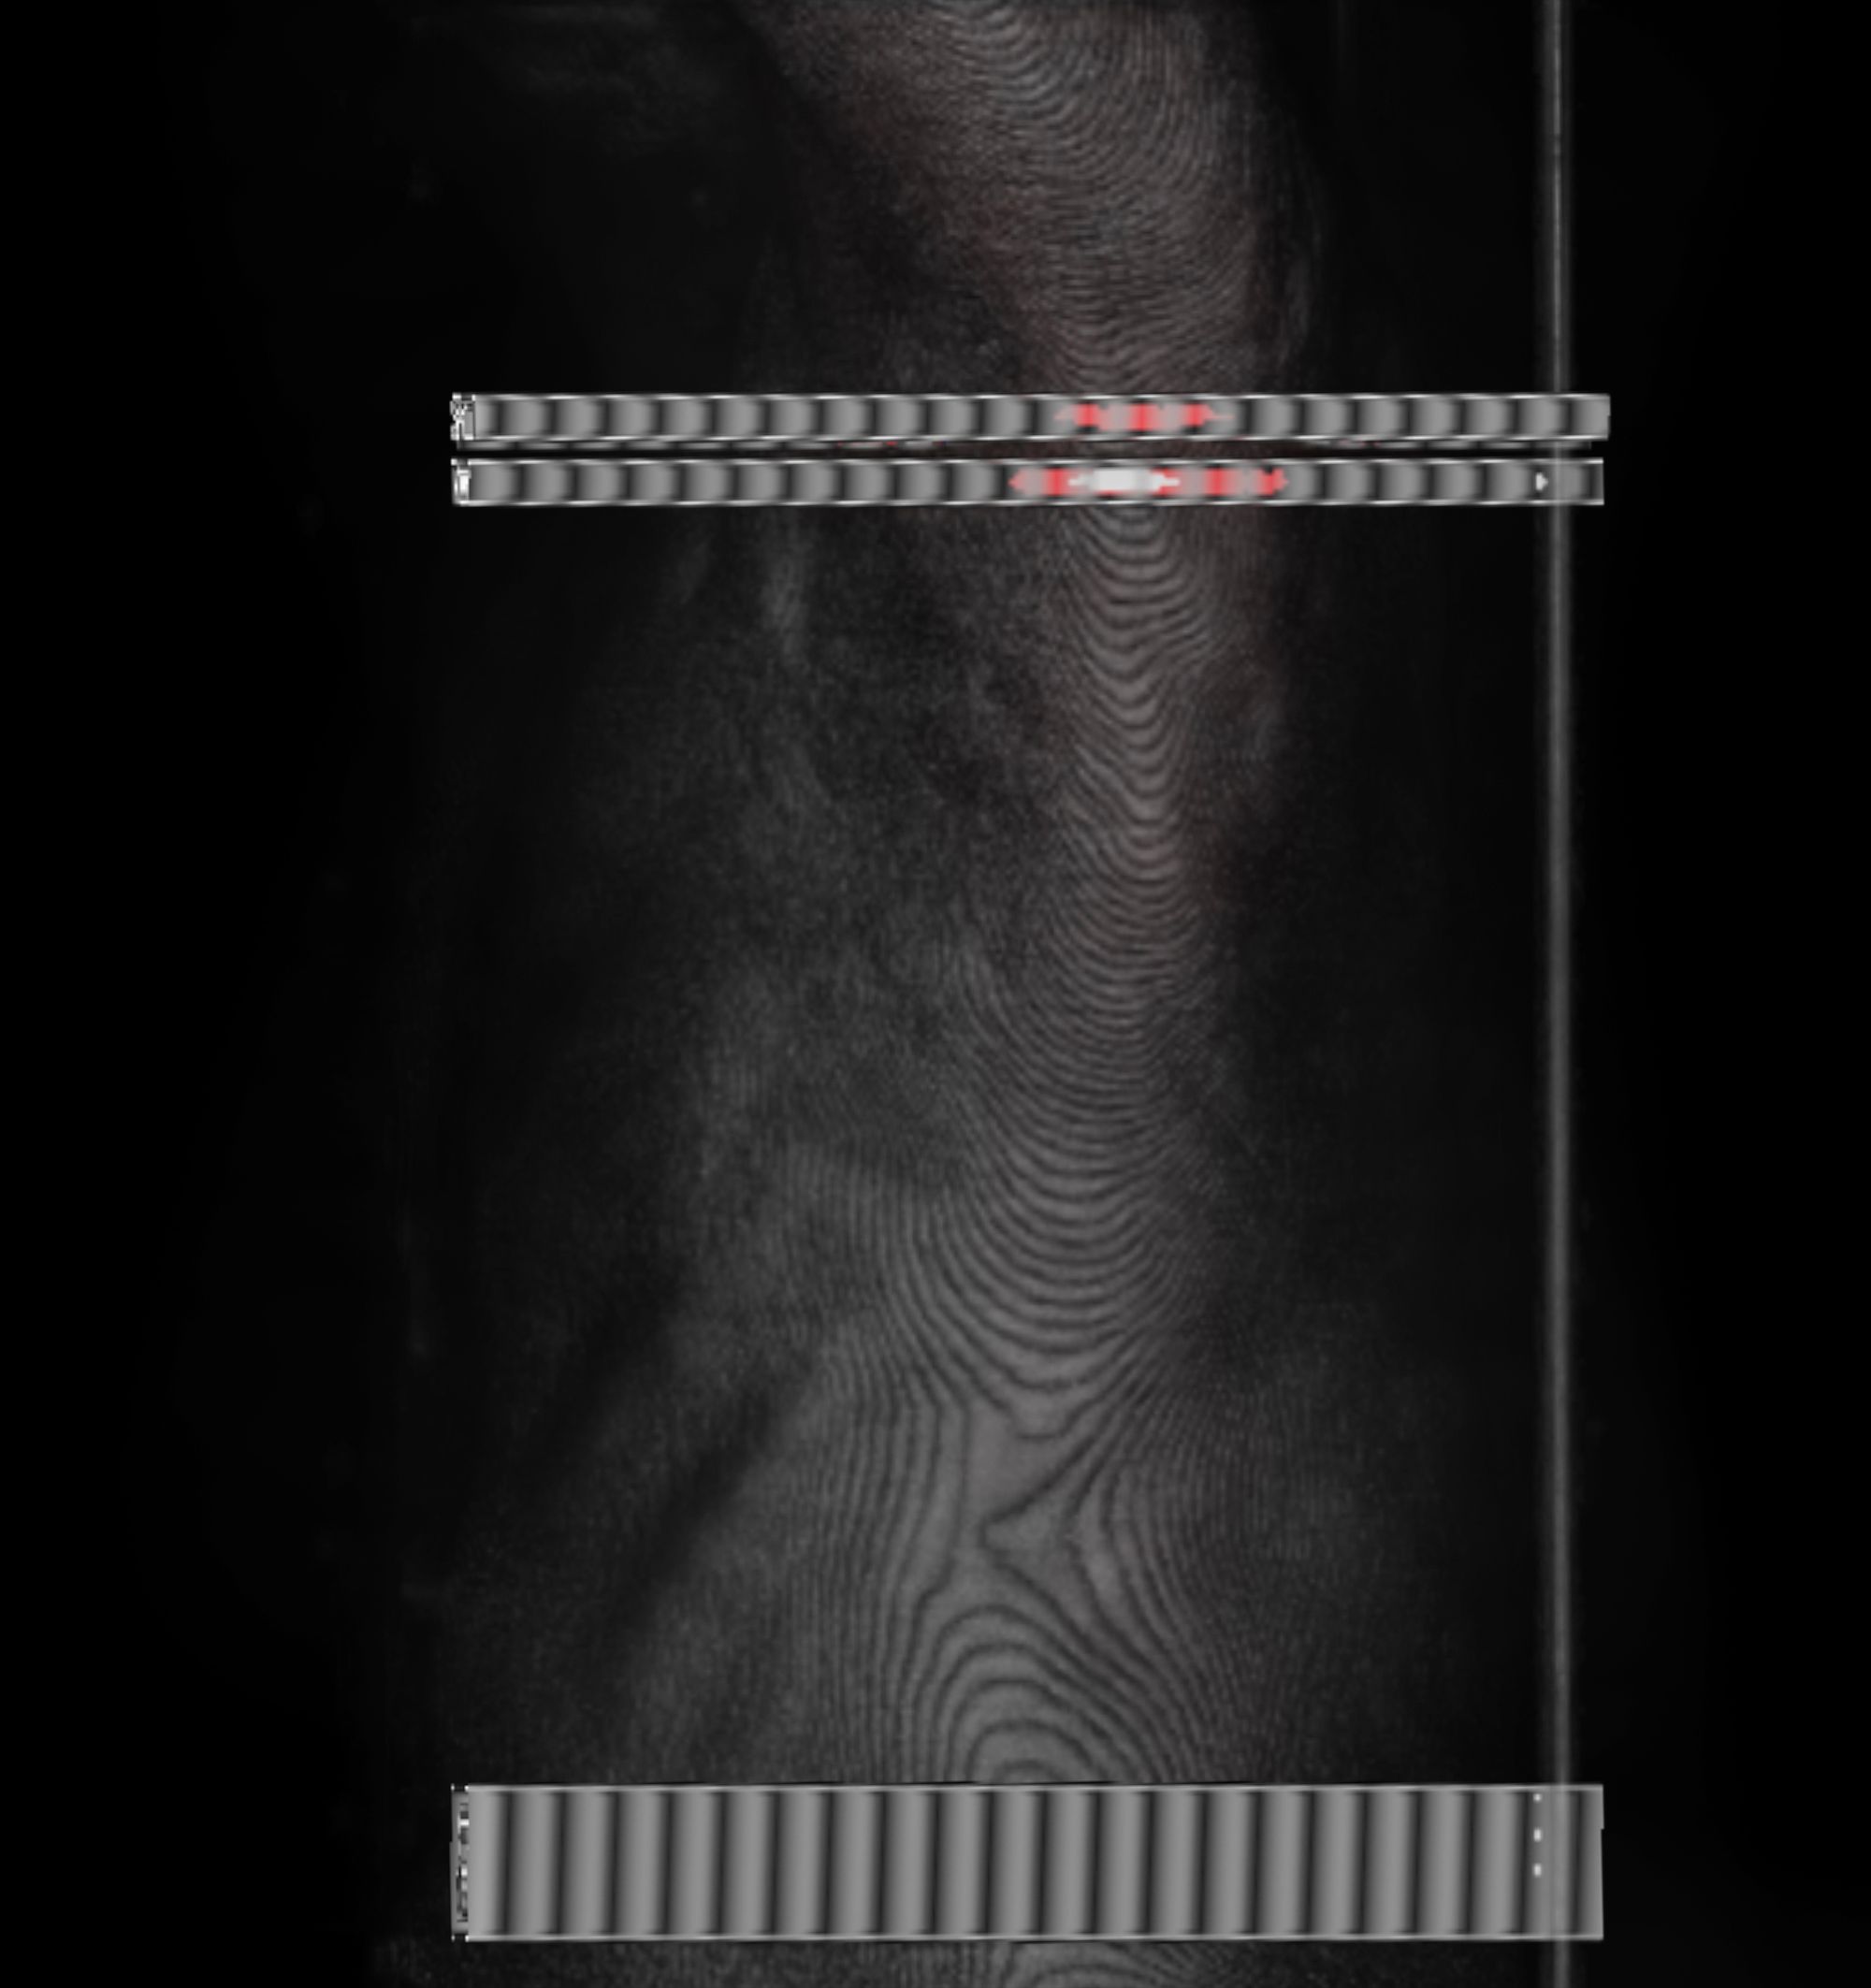

The history of medicine can be understood as an on-going endeavour to comprehensively visibilise the body, to pull it from obscurity, to open it out to vision. ‘The x-ray image, with its simultaneous view of the inside and outside, turned the vantage point of the spectator-subject inside out.’ * With the invention of the x-ray, the surface of the body, and its distinction from the world, was dissolved and lost in the image.

In this project, I look at the visual limit between the inside and the outside, the inner and the outer. I combine different visual approaches to materialise the body, using medical imagery, photography from manuals and radiology software. Decontextualised from their origin, these images speak of medicine’s relationship to both sex and violence, and remind us that, in medicine, to go into the body is always to go into the image first.